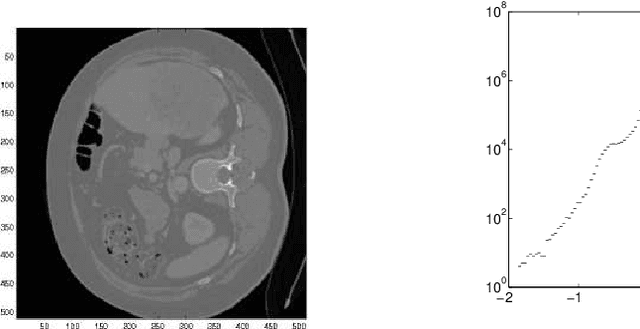

Abstract:The purpose of this paper is to introduce an algorithm that can detect the most unusual part of a digital image in probabilistic setting. The most unusual part of a given shape is defined as a part of the image that has the maximal distance to all non intersecting shapes with the same form. The method is tested on two and three-dimensional images and has shown very good results without any predefined model. A version of the method independent of the contrast of the image is considered and is found to be useful for finding the most unusual part (and the most similar part) of the image conditioned on given image. The results can be used to scan large image databases, as for example medical databases.